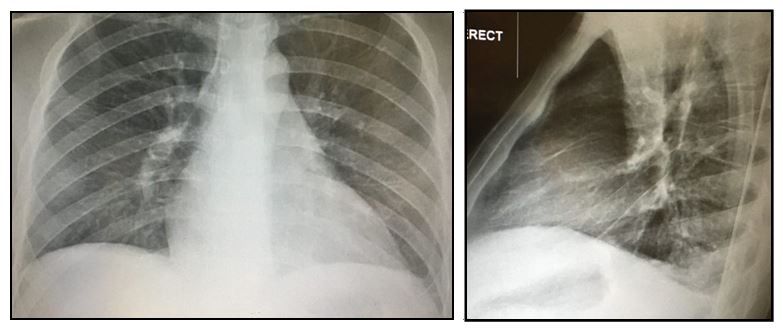

A 19-year-old previously healthy man presents with intermittent diarrhea, fever, and weight loss with pleuritic left-sided chest pain for 1 month. What does the chest x-ray show?

A 19-year-old previously healthy man is brought to the emergency department (ED) by his mother for 3-4 months of experiencing intermittent diarrhea and fevers up to 100.8°F with an associated 50-lb weight loss. The fevers are frequent, but not daily. He has also been having pleuritic left-sided chest pain for approximately 1 month. He denies cough, abdominal pain, vomiting, blood loss, or other complaints. He has been to other hospitals multiple times and no diagnosis was made but his symptoms continue to worsen.

Chest x-ray: See image above (please click to enlarge)

Discharge diagnoses: Serositis (pleural effusions, ascites), leukopenia, anemia with thrombocytosis, and microscopic hematuria with new acute kidney injury with results of a renal biopsy showing lupus nephritis.